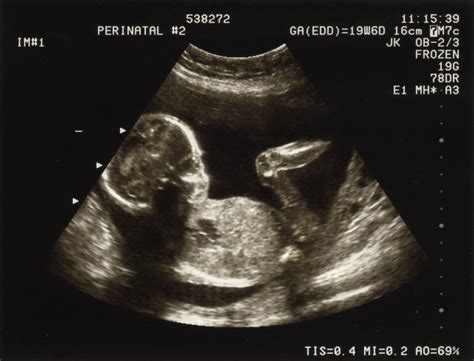

Pentru verificarea stării sarcinii în stadiile incipiente, se poate recurge la ecografie. Medicul poate recomanda și teste suplimentare, cum ar fi analize de sânge pentru evaluarea nivelurilor hormonale, oferind o imagine completă asupra stării de sănătate a mamei și fătului.